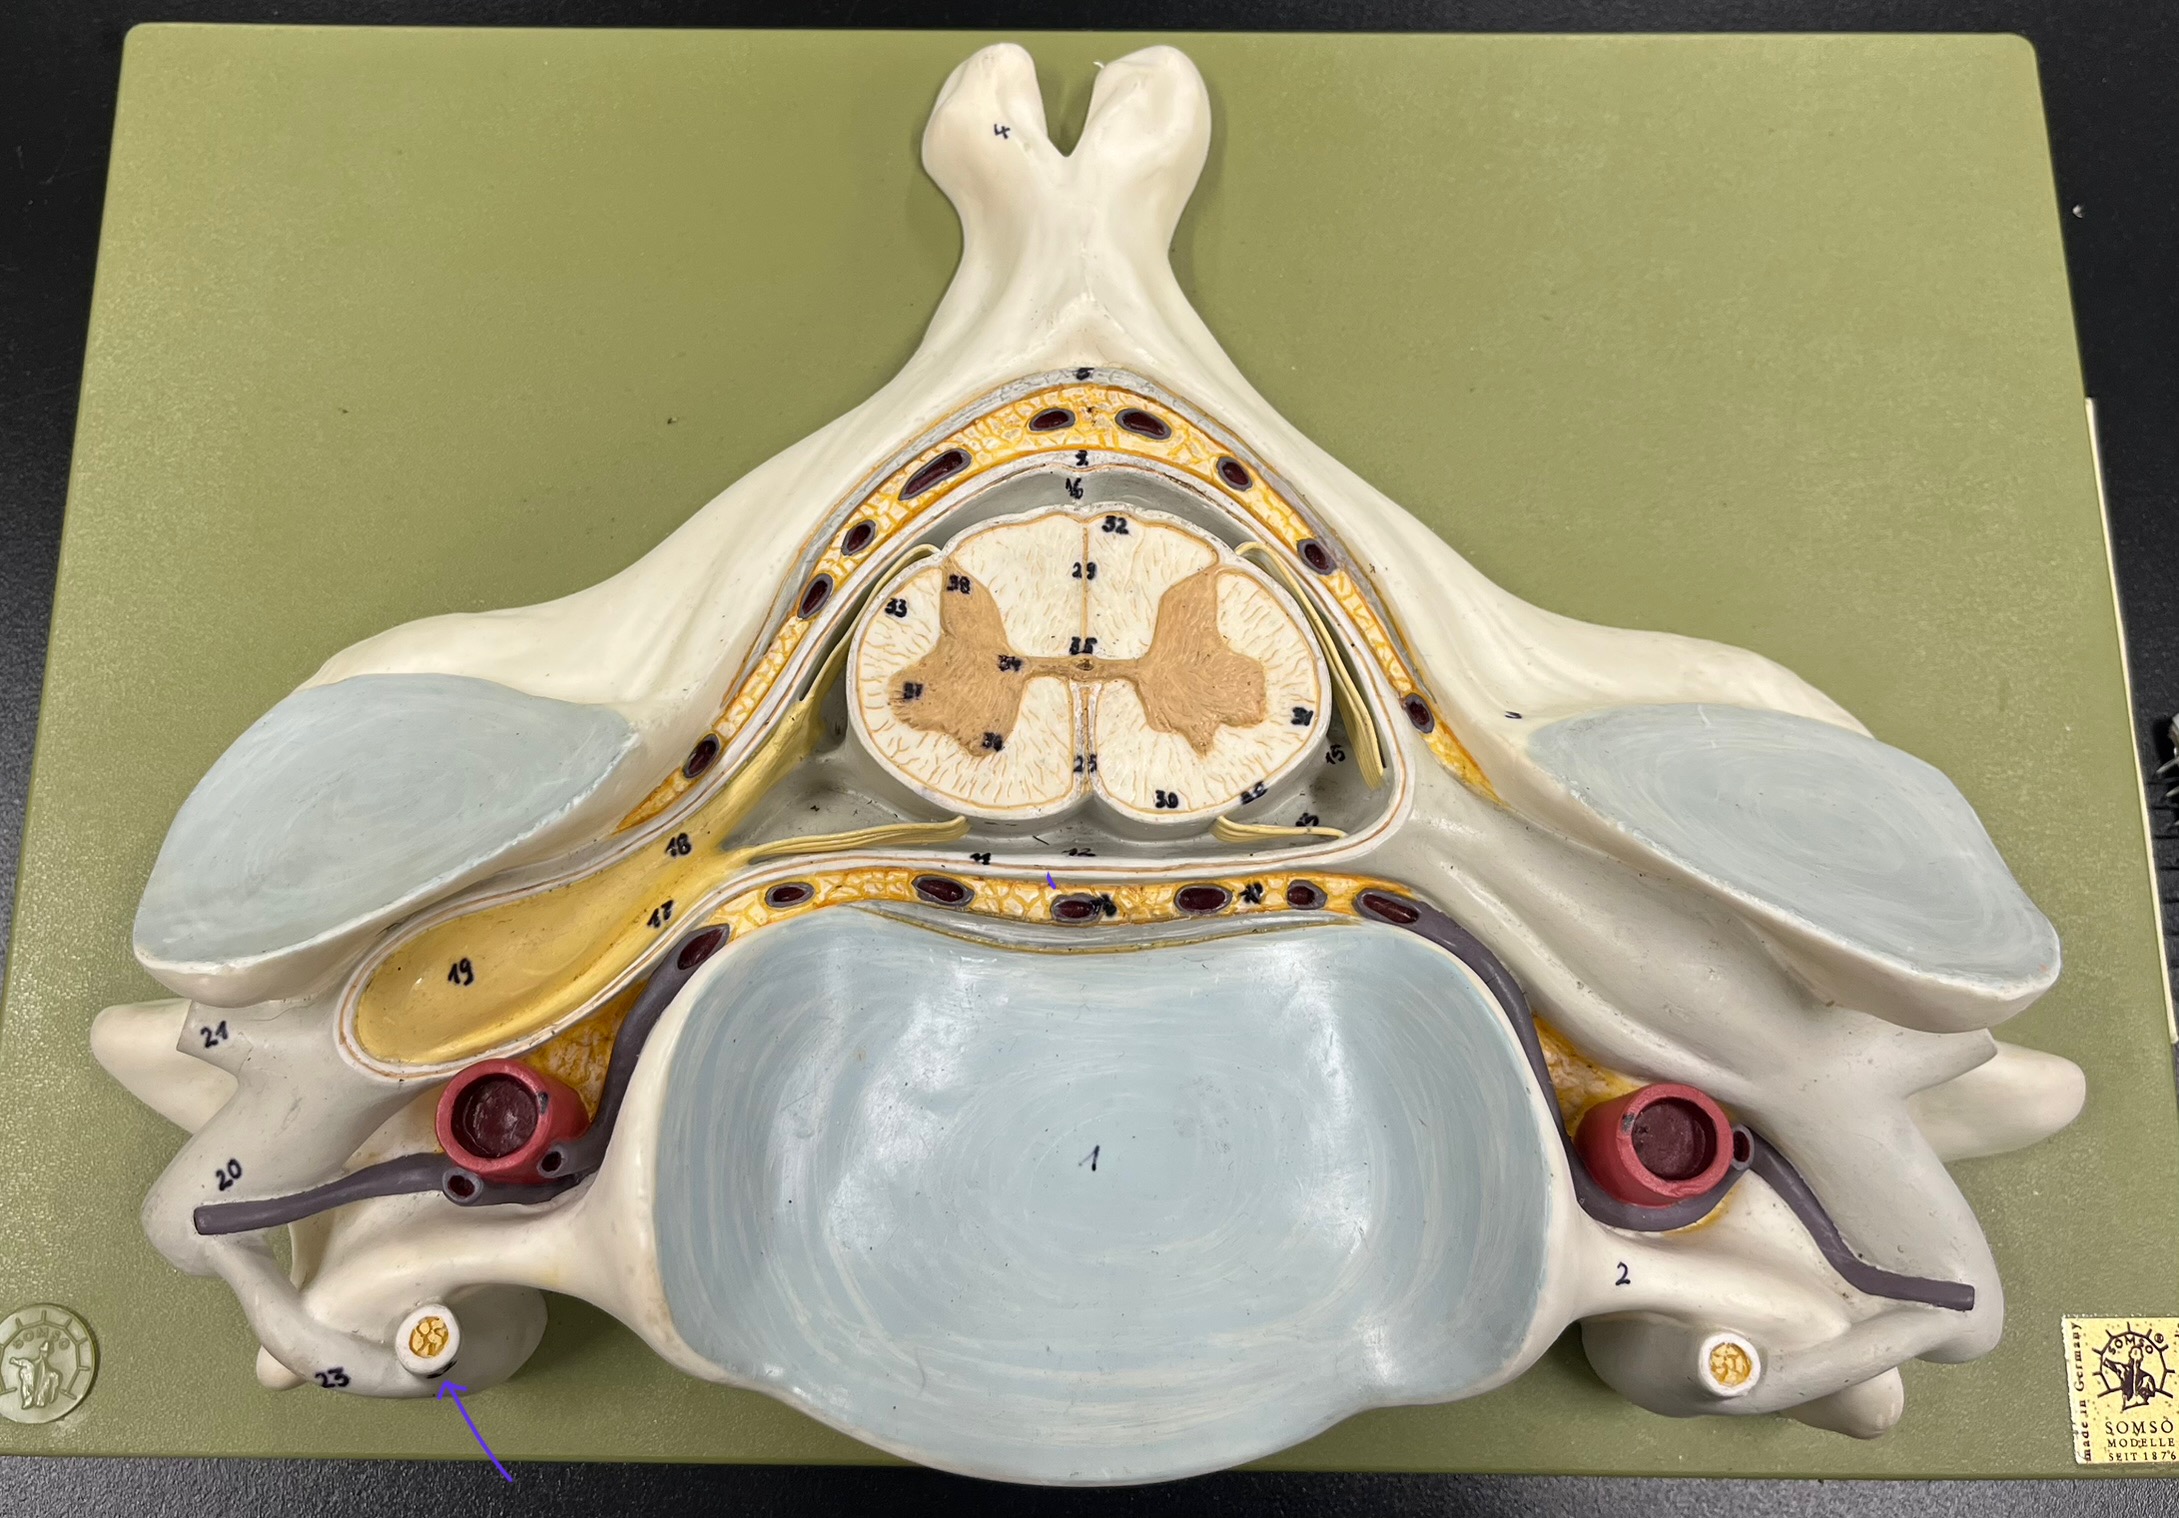

epidural space

dura mater

subdural space

arachnoid mater

subarachnoid space

pia mater

denticulate ligaments

anterior median fissure

posterior median sulcus

posterior (dorsal) horn

posterior (dorsal) horn; R—>L

anterior (ventral) horn

lateral horn (selected models)

gray commissure

central canal

anterior column

lateral column

posterior column

white commissure